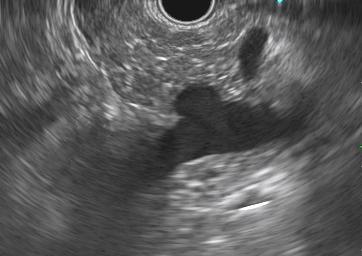

O diagnóstico no EUS se deu pela imagem pancreática hiperecoica difusa ou salteada, com borramento de seus limites e difícil caracterização do ducto pancreático principal ao invés do aspecto em “sal e pimenta” bem delimitado habitual – veja as imagens ilustrativas abaixo:

Imagens ilustrativas: